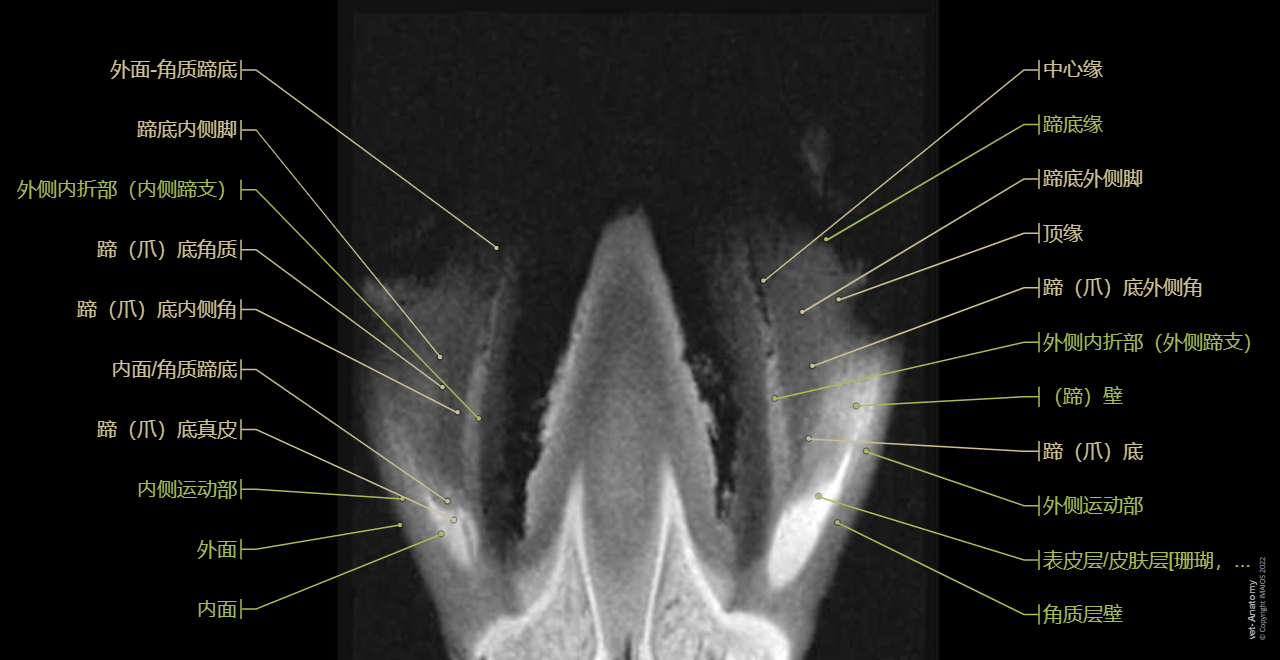

Foot and hoof anatomy of the horse on MRI (MRI - Flash-T1-FS-3D): Limbus, Corona of hoof [Coronet], Wall, Sole, Digital pad, Footpad, Frog, Hoof capsule, Digital cushion

• 质子密度加权像和T2-Stir序列都无法正常显示角膜结构如蹄壁、蹄底。我们本着教学目的选择去标记这些结构,所以在核磁共振图片的空白区域会见到部分标记。在单元结尾我们加入了3D图片,用户可以直接看到所有马蹄底的结构。

这单元的马足趾核磁共振解剖图是由Gwendolyn J. Levine(DVM, DACVP)提供。德克萨斯A&M大学的兽医与生物医学学院使用Siemens Verio 3T核磁共振机器扫描美洲奎特马正常左前腿。